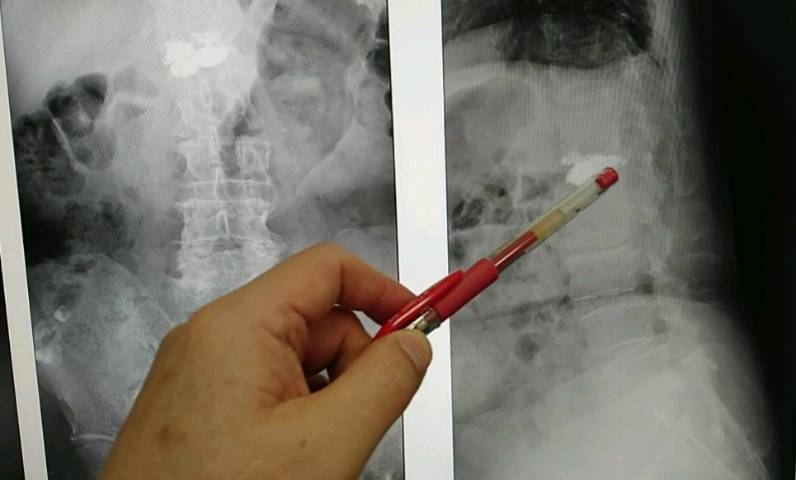

【記者于郁金/臺中報導】73歲曾姓女患者,練瑜珈有30多年,上個月卻因下背疼痛到骨科求診,醫師經X光檢查發現,患者的第一腰椎嚴重骨折,詢問下才得知,原來她是在瑜珈下課後自己練習高難度的「犁鋤式」動作,沒想到當時的「喀聲」竟是骨折聲。

豐原醫院骨科醫師江福財表示:瑜珈的「犁鋤式」動作,是將下肢整個雙腳屈膝上提,利用腹部肌群與骨盆力量,從尾椎開始慢慢將脊椎一節一節往上捲,將腿往頭頂做曲折,如果沒人在旁指導則容易受傷,患者才會導致胸、腰椎的交接處骨折。

一般人最常骨折的地方是在第一、第二腰椎處、和十、十一及十二胸椎處,以人體的脊椎結構來看,胸椎是一個前傾的角度、腰椎是一個後傾的角度,如果受傷最大常見的反應就是痛,嚴重者會壓迫到神經,導致下肢無力等情形。